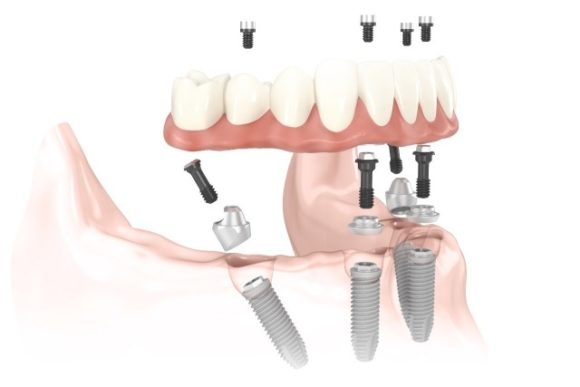

Ezt tudja a nem kivehető, csavarral rögzülő All on 6 fogpótlás

Bár az eredeti all on 4 technika csupán 4 implantátum beültetését igényelte, azonban fontos tisztában lenni azzal, hogy minél több implantátum kerül beültetésre, annál jobbak az esélyek arra, hogy megbízhatóbb, stabilabb és biztonságosabb legyen a csavarokkal rögzített fogsor.

S mivel ez a csavaros típusú fogpótlás otthon nem eltávolítható, így rendkívül fontos, hogy a folyamatos terhelést megfelelő számú implantátum viselje. Klinikánk szájsebészei ezért a tartósabb és hosszú távon sikeresebb all on 6 fogpótlást ajánlják a hagyományos all on 4 fogsor helyett.

Az All on 6 fogsor egy rendkívül precíz gyártási folyamat eredménye. A fogpótlás a saját fogakra is megtévesztésig hasonlító porcelánból készül és az implantátumokban rögzülő felépítményekhez (csonkokhoz) a porcelán fogpótlás (porcelán híd) csavarokkal rögzül.

A csavarokkal rögzülő All on 6 előnyei:

- 6 db implantátumra épülő rögzített, speciális porcelán korona híd

- Egyáltalán nincs, vagy csak minimális csontpótlásra van szükség.

- Stabil, csavarokkal rögzített, nem kivehető pótlások.

- Gondtalan rágás, normális hangképzés és természetes esztétikai hatás.

- Könnyű gondozás.